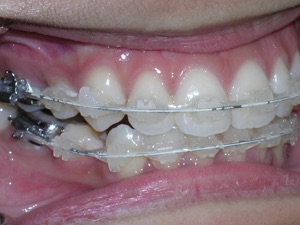

Here are the porcelain braces applied.